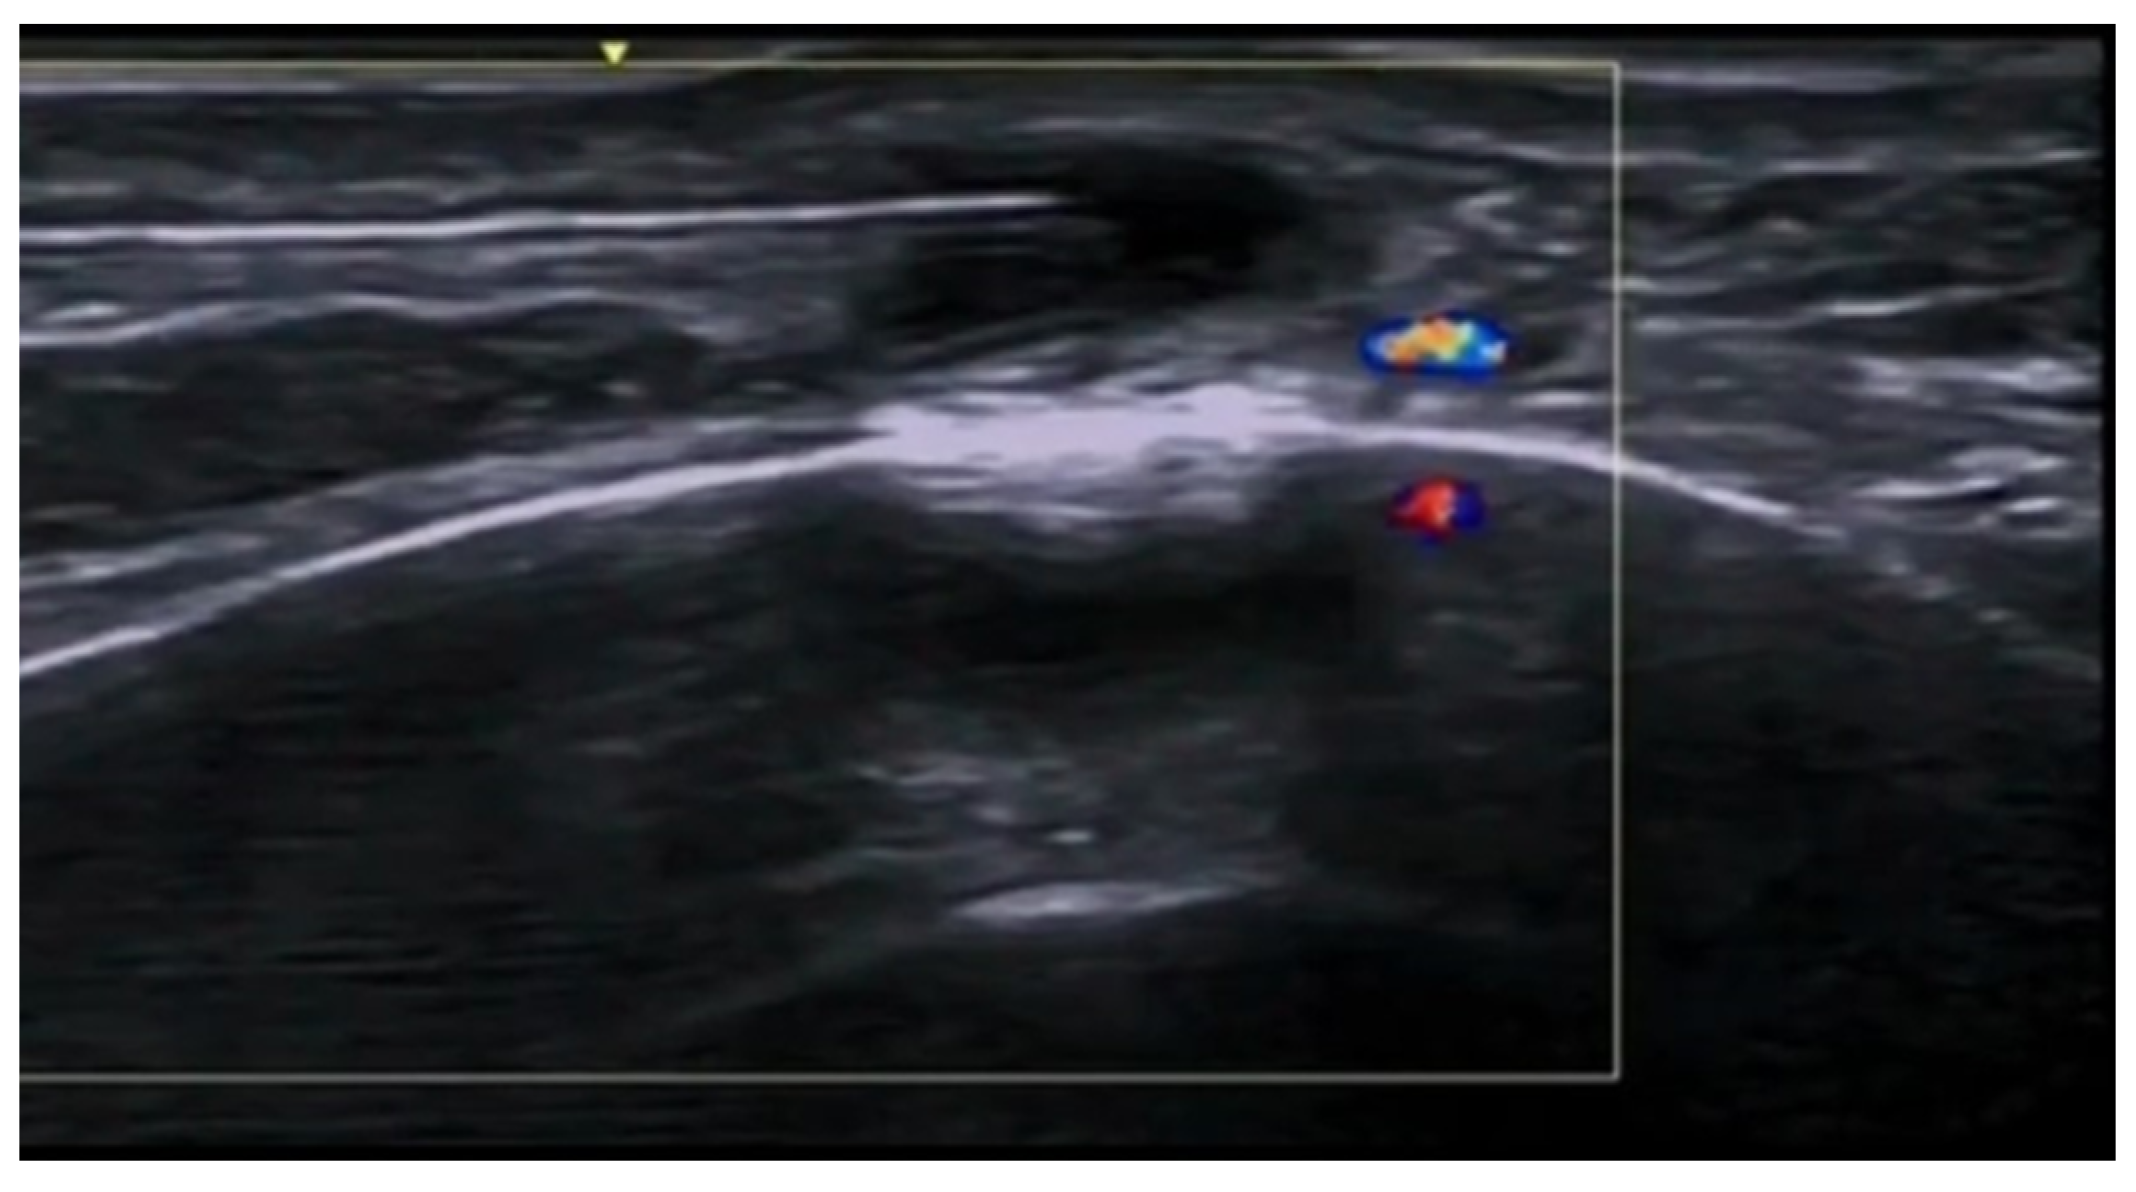

- Parra-Cares, J.; Wortsman, X.; Alfaro-Sepúlveda, D.; Mellado-Francisco, G.; Ramírez-Cornejo, C.; Vera-Kellet, C. Color Doppler Ultrasound Assessment of Subclinical Activity with Scoring of Morphea. J. Cutan. Med. Surg. 2023, 27, 454–460. [Google Scholar] [CrossRef] [PubMed]

- Wortsman, X.; Vera-Kellet, C. Ultrasound Morphea Activity Scoring (US-MAS): Modified US-MAS. J. Ultrasound Med. 2023, 42, 2447–2450. [Google Scholar] [CrossRef] [PubMed]